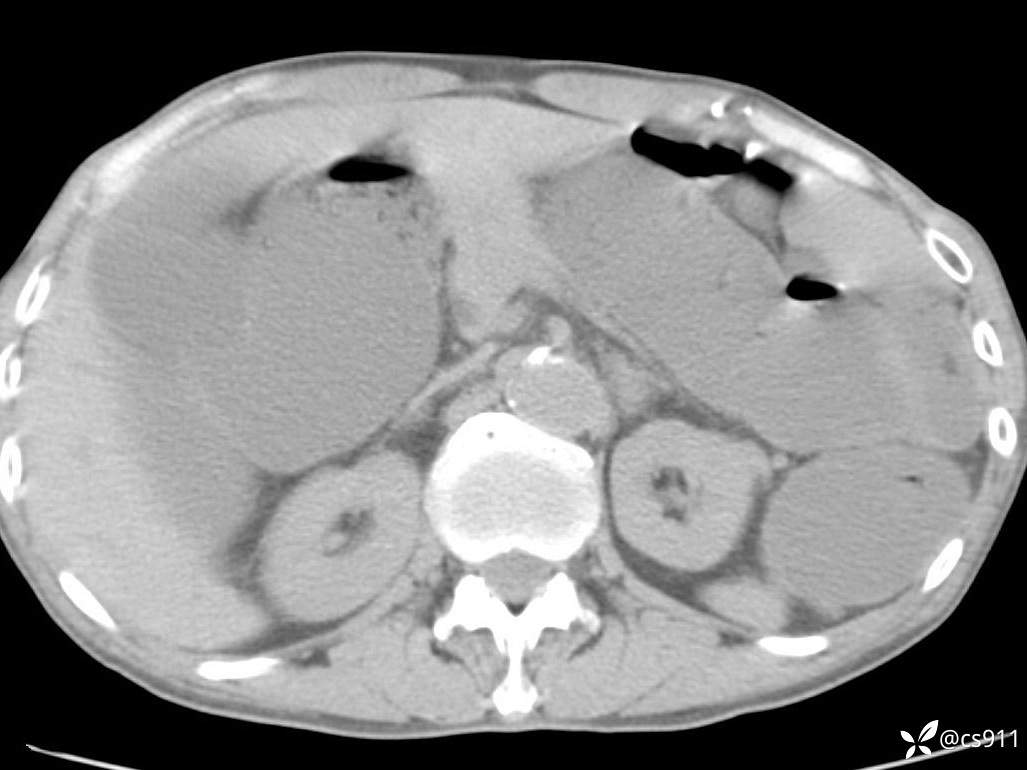

急腹症之急诊CT,原因?答案公布

男,77岁,腹痛、腹胀伴恶心呕吐1天。呕吐胃内容物,非喷射性呕吐,有咖啡色样胃内容物,诉有胃穿孔病史。查体:全腹平,下腹部压痛,全腹无反跳痛,叩诊呈浊音,移动性浊音阴性,肠鸣音减弱,1-2次/分。肛检:直肠未扪及明显肿物,可触及大量粪块。

血淀粉酶(AMY) HH 1859 U/L 35-135